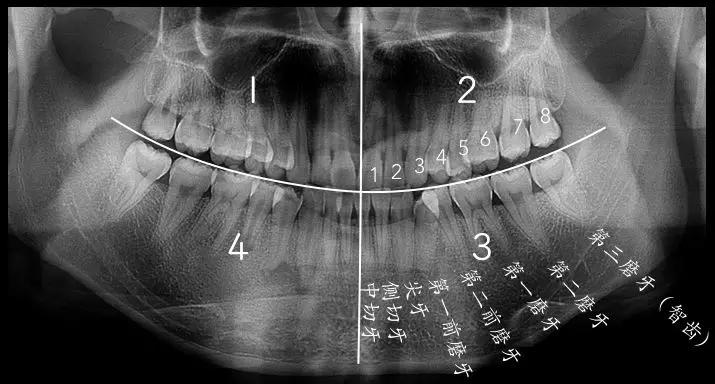

1.常见智齿的形态

智齿是从正中的门牙往里数第八颗牙齿,也就是第三颗磨牙。它是发育、萌出最晚的牙齿,通常在4~5岁时形成牙胚,随后逐渐发育形成牙齿,一般17~25岁左右萌出,此时人的生理、心理发育都接近成熟,因此俗称“智齿”。

智齿的形态也是各种各样,简单可以罗列如下几种,实际复杂远不止以下